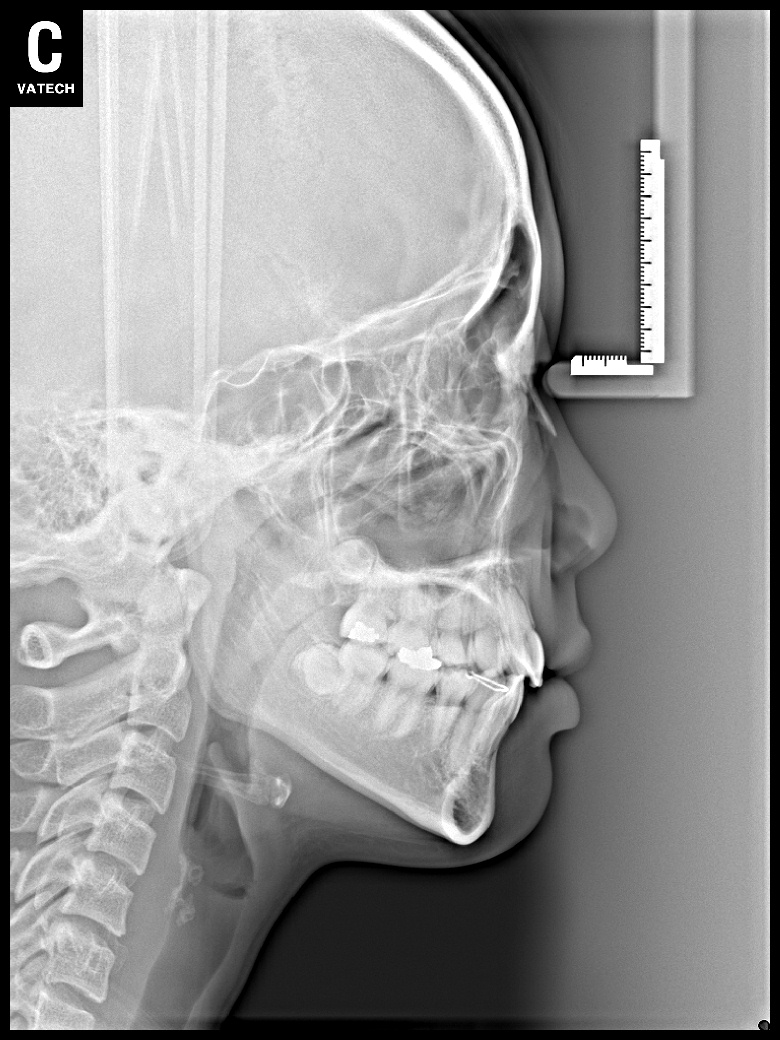

치료 전 사진입니다.